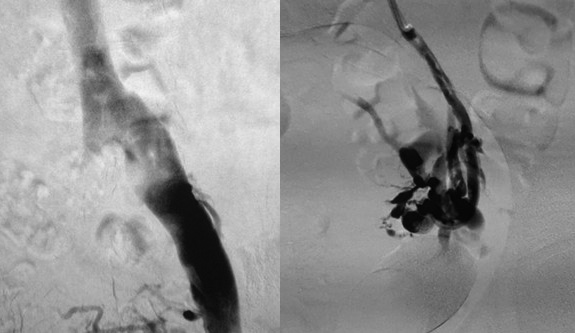

Aneurismas Arteriais

caracterizados pela dilatação de uma ou mais artérias, excedendo em 50% o diâmetro normal do vaso. Dentre as suas principais causas encontram-se o tabagismo….